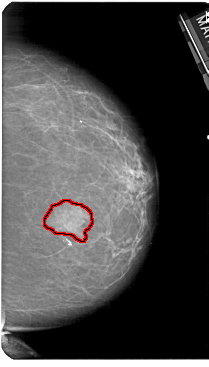

A_1182_1.RIGHT_CC

RIGHT_CC LINES 5491 PIXELS_PER_LINE 3121 BITS_PER_PIXEL 12 RESOLUTION 43.5 OVERLAY

FILE: A_1182_1.RIGHT_CC.OVERLAY

TOTAL_ABNORMALITIES 1

ABNORMALITY 1

LESION_TYPE MASS SHAPE IRREGULAR MARGINS ILL_DEFINED

ASSESSMENT 4

SUBTLETY 5

PATHOLOGY MALIGNANT

TOTAL_OUTLINES 1

BOUNDARY